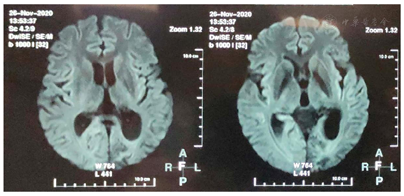

患者,女性,37岁,主因"间断抽搐发作36余年,加重5月余"于2020年11月24日就诊于河北医科大学第二医院神经内科。患者于6月龄时出现抽搐发作,表现为双眼向右上偏斜,四肢抽搐,伴意识不清,呼之不应,持续约数小时缓解。后此症状间断发作,表现同前,每次共3 h左右,发作频率约1次/20 d,共发作3次后未再发作。8月龄时出现发作性肢体活动障碍,表现为哭闹时仅一侧肢体活动,意识清楚,偏瘫侧肢体软,左右侧肢体交替发作,单侧偏瘫持续3天左右交替至另一侧,每次共持续1周左右,发作频率约半个月1次,就诊于当地医院,诊断为"低钙抽搐",给予补钙治疗,症状未见明显好转。1岁半时就诊于北京数家医院,于首都医科大学宣武医院完善头颅CT检查未见明显异常(具体不详),予以口服药治疗(具体不详),服用完后自行停药。后间断就诊于当地医院,诊断为"癫痫",15岁左右开始口服抗癫痫药物(具体不详)。11年前(26岁时)口服卡马西平0.2 g、2次/d,出现发作性肌张力障碍,表现为双上肢伸直,双手腕屈曲外旋,偶伴头眼右偏,意识清楚,为成簇发作,约半个月1簇,3~5 d/簇,数次/d,每次持续约数分钟,月经前或情绪不稳定时易发作;交替性偏瘫发作症状逐渐演变为发作时偏瘫侧肢体伴有强直性肌张力障碍,右侧肢体发作时症状常较左侧重。逐渐停用卡马西平(共服用数月),上述症状仍间断发作,发作表现及频率同前,就诊于北京数家医院,于北京三博脑科医院完善头颅核磁共振、24 h视频脑电图、48h视频脑电图和脑磁图等检查,家属回忆视频脑电图示未见癫痫样放电,头颅核磁共振示有病灶,脑磁图示病灶位置较深不宜手术(因检查结果及报告丢失,具体不详),诊断为"运动障碍性疾病",予以口服美多芭治疗,症状未见好转,数月后自行停用。此后数年间患者除交替性偏瘫发作、肌张力障碍发作外间断于清醒状态下出现全面性强直-阵挛发作2次,发作前有头痛先兆,每次持续约30 min。入院5个月余前患者于清醒状态下突然出现右侧肢体抖动,伴头眼右偏,口角向右侧偏斜,意识丧失,伴流涎,持续约数小时,就诊于当地医院查头颅MR示左侧颞顶枕叶病变,性质待定,后此症状间断发作,偶伴小便失禁,发作前有恶心、呕吐等先兆,发作频率约1次/周,患者逐渐无法自行行走;入院3个月前患者发作形式变化为右手右脚抖动,伴右侧面肌、嘴角抽搐,每次持续约数小时,频率约1次/10 d。现患者口服"丙戊酸钠0.4 g、3次/d,左乙拉西坦每早0.75 g,每晚0.5 g"。个人史:足月顺产,系第一胎第一产,其母亲诉其出生受冻史;运动发育迟缓,6岁会走路;未婚未育,父母及2个妹妹体健。既往史:偏头痛病史20余年,未予诊治;甲状腺功能亢进症病史5年余,口服甲巯咪唑片治疗。月经史、家族史无特殊。入院神经系统查体示神清,智力发育、理解力较差,双瞳孔正大等圆,对光反射稍迟钝,双手肌张力障碍样姿势,右侧肢体肌张力稍高,四肢腱反射(+++),双侧巴宾斯基征(-),余查体不合作。

ATP1A3基因突变可导致生命早期严重癫痫[8]。约半数AHC患者合并癫痫,且多为耐药性癫痫,癫痫发作可与偏瘫发作同时发生或独立出现[2],癫痫类型和癫痫发作类型多样,癫痫发作甚至癫痫持续状态(SE)可以发生在其他类型的AHC发作之前,通常始于新生儿期[9]。携带E815K突变患者通常表现为更严重的AHC表型,癫痫和SE的发生率更高[2,9]。本例患者具备多种癫痫发作类型,常独立出现,多表现为SE,抗癫痫药物反应欠佳。AHC患者影像学表现通常是正常的,少数可出现大脑或小脑萎缩[9,10,11],值得注意的并遗憾的是,本例患者入院前2次于癫痫发作后行头颅MR检查示左侧颞顶枕叶病变,入院后复查头颅MR提示该病变呈可逆性,脑萎缩加重,线粒体环基因及核基因检测未发现突变,最终我们未能明确其性质及原因。国外1项队列研究中观察到1例患者在SE后24 h内进行MRI检查,出现右侧顶叶内侧T2加权液体反转恢复(FLAIR)序列灰质信号增强,并与发作期视频脑电图(EEG)异常及症状学相符,这与本例患者类似[9]。此外该研究还显示AHC患者EEG异常和癫痫样放电的发生率随着监测次数的增加而增加[9]。